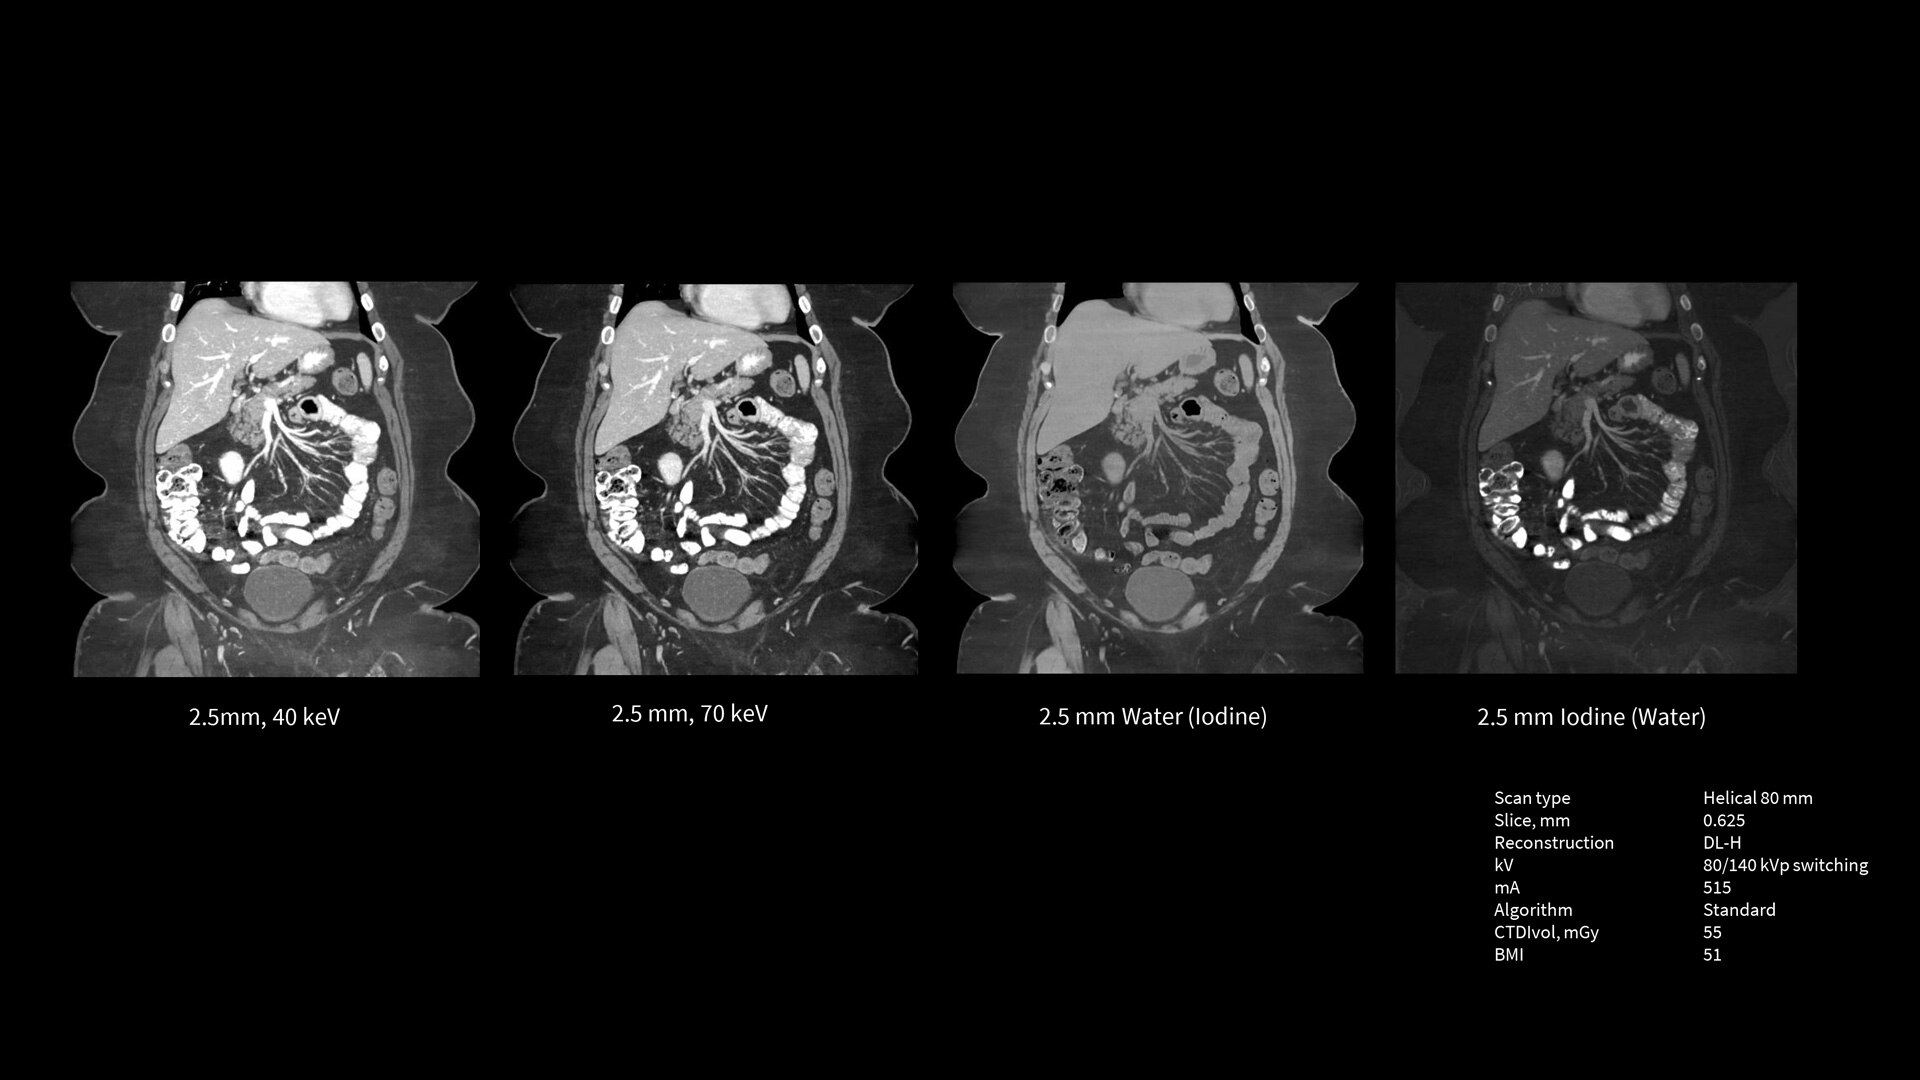

The Revolution Apex platform was built with exceptional technologies throughout the imaging chain and with an Effortless Workflow model of efficiency to help you meet your imaging challenges. To meet tomorrow’s needs, we’ve built it with scalable detectors that allow you to take your practice to the next level at any time. The Revolution Apex platform is the powerful, adaptable technology you need to lead CT now and into the future.

Scalable Clarity Detector

The Revolution Apex platform has a modular design that allows for hardware scalability. You can start with Revolution Apex Select with a 40mm detector and in the future, when you need to grow your service line, you can scale the detector up to 160mm.